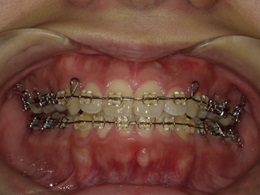

治療中正面

治療中左側

右側治療中